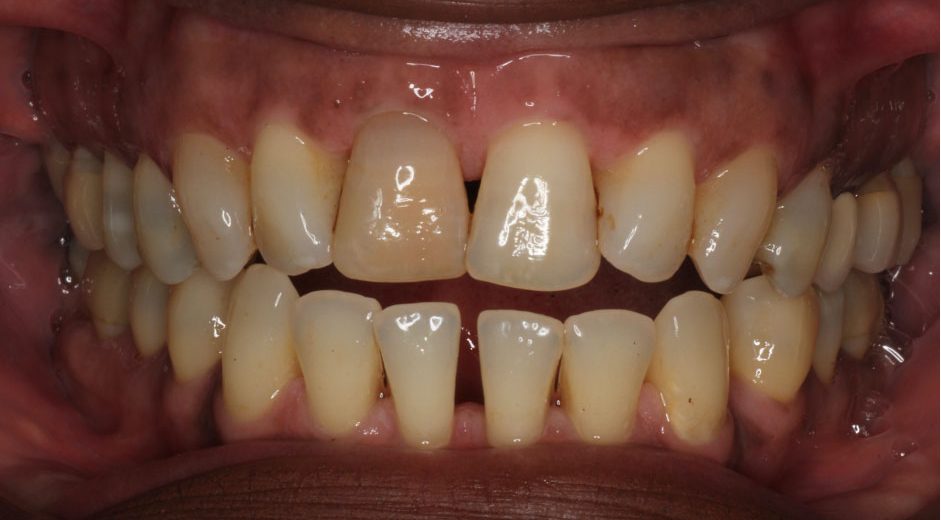

- Class III incisal relationship

- In patients with a class III incisal relationship, it is very difficult, if not impossible, to design an occlusal scheme with canine guidance

- Anterior open bites

- Similar to those with class III relationships. It is impossible to design a canine-guided occlusal scheme in these patients (see Figure 3)